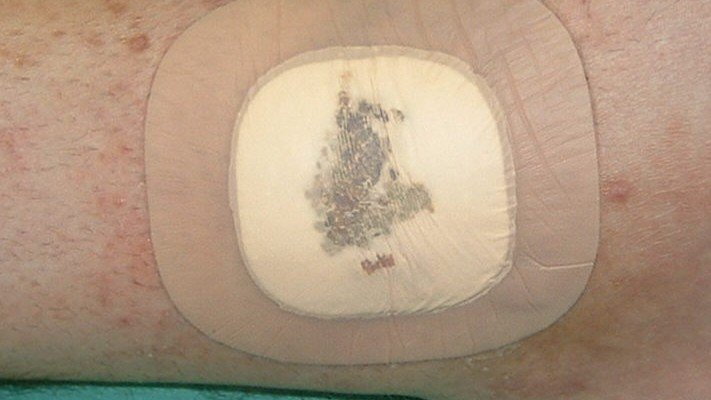

Superabsorbierende Mehrkomponenten-Verbände

Zusätzliche Fotos ![]() 1

1

Superabsorbierende Wundauflagen

Zusätzliche – Fotos ![]() 24 Videos

24 Videos ![]() 2

2![]() Fallbeispiele

Fallbeispiele